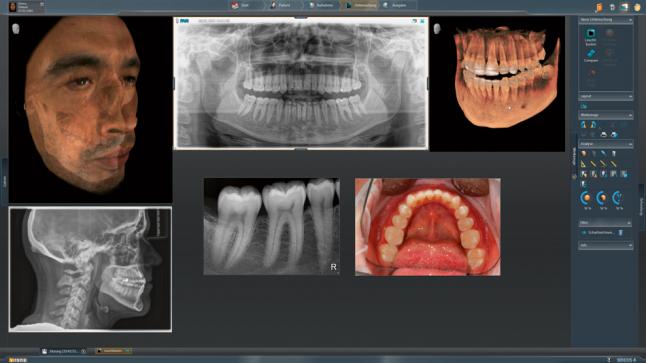

Модернизированный сенсорный экран Easypad с понятным и удобным интерфейсом позволяет выставить наилучшие параметры контрастности и разрешения. Систематизация данных по диагностике становится значительно удобнее и проще с ПО обработки изображений SIDEXIS 4, ORTHOPHOS.

1. Двух-и трёхмерные снимки совмещаются в одной программе

2. В одном окне можно сравнивать разные 3D-результаты

3. Считанные минуты уходят на просмотр анамнеза пациента.

Временная шкала Timeline – это мгновенное получение информации полного спектра проведённых обследований пациента в порядке хронологии. В результате – экономия рабочего времени и повышение качества работы в целом.